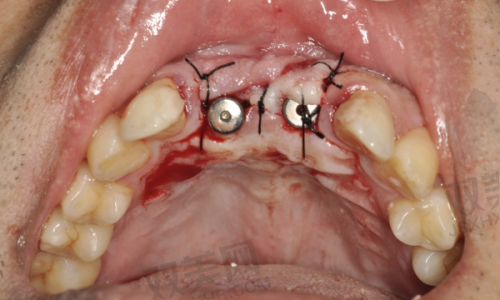

种植体植入手术

在局部麻醉下,医生会在患者的牙槽骨上制备一个合适的种植窝,然后将种植体植入其中。手术过程中,医生会严格遵循无菌操作原则,确保手术的安心性。植入种植体后,患者需要等待一段时间,让种植体与牙槽骨形成骨结合,这个过程一般需要3 - 6个月。